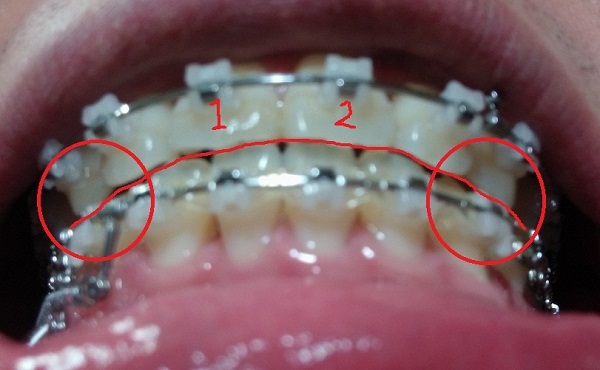

이렇게 사진으로 보니 확연한 구분은 가지 않지만

현재 오른쪽 부분이교정장치를 제거 했음에도 불구하고 살짝 떠 있죠..?

현재 이 부분(빨간부분)이 병원과 저와의 만족선? 합의점?이라고 해야 될까요?